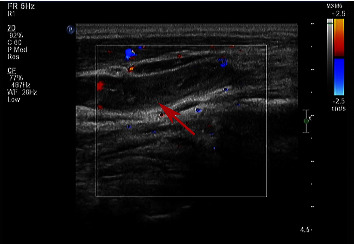

Abstract Image